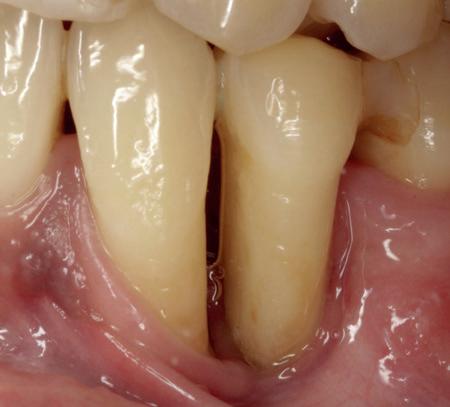

Uit het röntgenonderzoek blijkt dat op de locatie van de 22 veel bot verloren is gegaan en dat er niet direct een implantaat geplaatst kan worden. Om die reden is een botaugmentatie geïndiceerd. Wel zijn distaal van de 21 en mesiaal van de 23 de botpieken aanwezig die de papillen ondersteunen. Naast te weinig bot, is op de locatie 22 in bucco-linguale richting ook te weinig volume gingiva aanwezig. Daarom zal er tevens een soft tissue graft aangebracht worden. Tijdens deze behandeling wordt ook de recessie op de 23 zoveel mogelijk bedekt (foto 7 en 8).

De flap en graft worden met poly-propelene 6.0 hechtingen gefixeerd. De tijdelijke reconstructie wordt herplaatst (foto 17-20).

Na 4-6 weken kan het aangebrachte healing abutment worden vervangen door een tijdelijk abutment. Deze wordt aan de kunststof reconstructie verbonden om zo de gingiva ter plaatse van de 22 te vormen. Zo lijkt het of er geen implantaat maar nog steeds een wortel aanwezig is, wat het esthetisch eindresultaat ten goede zal komen (foto 21-23). Vanaf 4-6 maanden ziet het weefsel er gezond uit. Nu kan met de uiteindelijke restauratiefase worden gestart (foto 24 en 25).